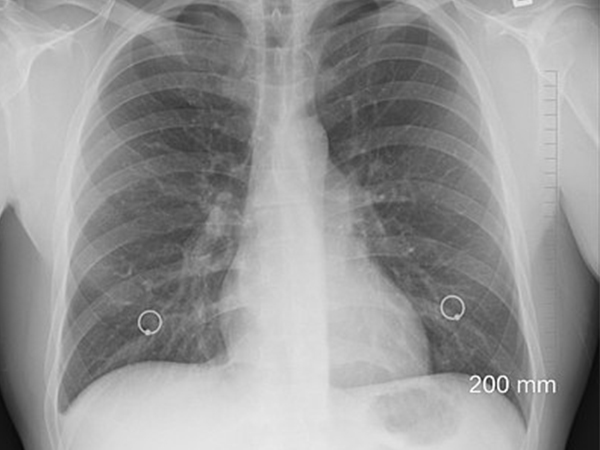

చెస్ట్ స్కాన్లు..

వ్యాధి తీవ్రతను గుర్తించడంలో హెచ్ఆర్ టి స్కాన్లు కచ్చితంగా బాగా పనిచేస్తాయని నిపుణులు చెబుతున్నారు. ఇది కోవిద్-19 వల్ల కలిగే ఊపిరితిత్తుల పనితీరు, సామర్థ్యాన్ని కూడా తెలియజేస్తుంది. కోవిద్ నుండి కోలుకున్న తర్వాత చాలా మంది ఊపిరితిత్తులు బాగా పని చేస్తున్నాయని వైద్యులు చెబుతున్నారు. అయితే కొందరికి మాత్రం వైరల్ ఇన్ఫెక్షన్ మరియు శ్వాసకోశ మద్దతుపై ఇవన్నీ ఆధారపడి ఉంటాయి. కాబట్టి ఈ స్కాన్ల వల్ల ఊపిరితిత్తుల పనితీరు పరీక్షలు చేయించుకోవడంలో సహాయపడుతుంది.